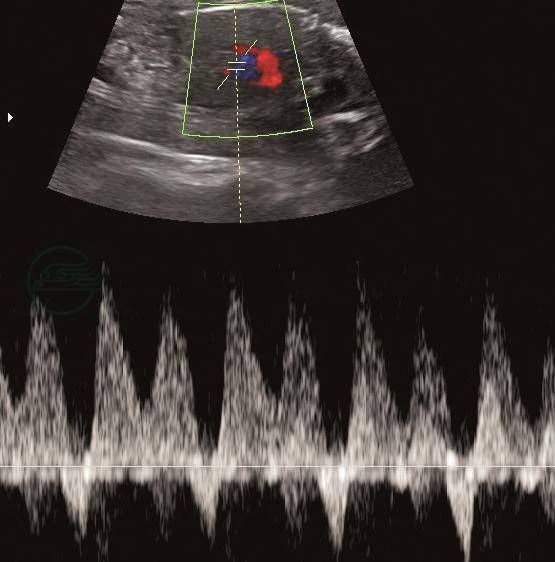

(4)静脉导管:严重FGR常合并胎儿心血管功能的改变,心前静脉的血流模式取决于心脏的顺应性、收缩力及后负荷,心房收缩波(a波)降低、消失和反向提示胎儿心脏功能受损(图4)。静脉导管血流评估对新生儿酸中毒和不良结局有一定预测价值。

图4静脉导管

妊娠26+6周,静脉导管a波反向